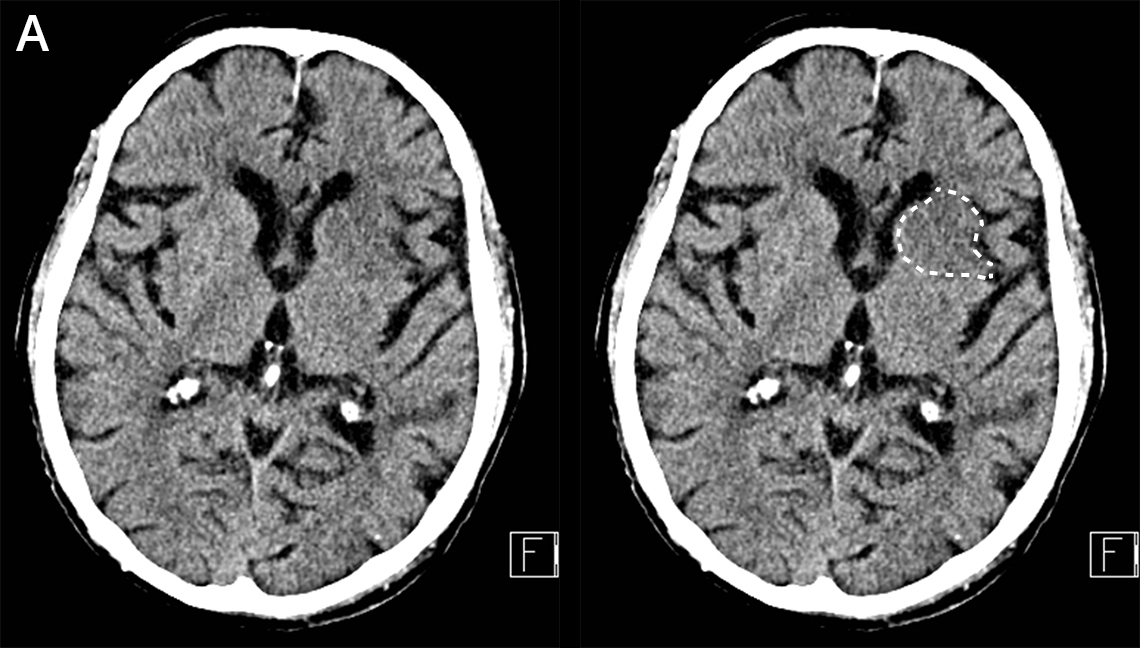

Aivoinfarkti pään TT-kuvassa MCA:n suonitusalueella.

Iäkäs mies kaatui ja löi päänsä. Potilaalla oli ennestään vanhan aivoinfarktin pohjalta oikean puolen heikkoutta. Kaatumisen jälkeen tajunnan taso oli lievästi laskenut ja oikea puoli oli tavallistakin voimattomampi.

A. Pään TT:ssä vasemmalla puolella on nähtävissä harventumaa a. cerebri median suonitusalueeseen kuuluvalla basaalitumakealueella (valkoinen katkoviiva). Hento harventuma sopii tuoreeksi infarktiksi em. alueella. Vuotoja tai likvorkierron häiriöitä ei ole nähtävissä

Kuvat: HUS Kuvantaminen, teksti: Tiina Lehtimäki